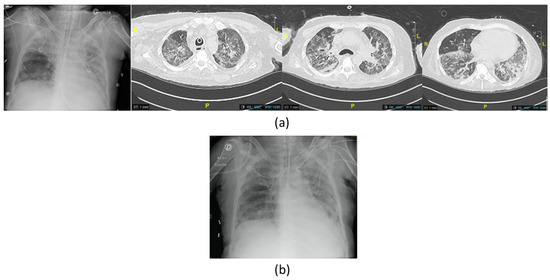

Figure 2. Imaging of the third episode of VAP due to XDR P. aeruginosa with (a) chest X-ray showing right apical opacities and computed tomography scan (CT scan) before the first phage therapy showing bilateral extensive diffuse pneumonia of the lungs; (b) chest X-ray at the end of the treatment showing improvement.